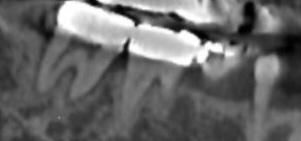

• 3번 째 사진

뼈는 녹아 있는 것이 확인됩니다. 치아를 살리시고 싶으시면 잇몸치료 선행해보셔도 괜찮습니다.